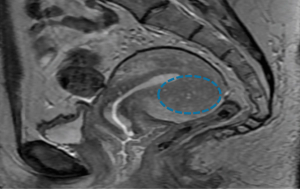

Adenomyosis and its impact on fertilityByAnthony N. Imudia, MD,Rachel G. Sprague, MDNovember 16th 2018Comorbidities such as endometriosis can confound the picture in patients with adenomyosis, a condition that may lead to poor IVF outcomes.